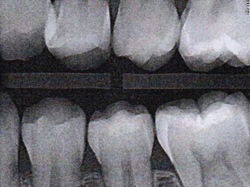

Fig 3. Three thin soft dental picks were used simultaneously for SDF proximal surface saturations in a teenaged patient (Fig 3). After 60 seconds, the treated regions were covered with 5% fluoride varnish (Fig 4). A comparison can be seen of pre-SDF-treatment bitewing films (Fig 5) and 8-month post-SDF bitewing films (Fig 6) for the patient shown in Fig 3 and Fig 4. Radiolucencies were similar or improved, except for contact of maxillary first and second molars.

Figure 3

Fig 5. Three thin soft dental picks were used simultaneously for SDF proximal surface saturations in a teenaged patient (Fig 3). After 60 seconds, the treated regions were covered with 5% fluoride varnish (Fig 4). A comparison can be seen of pre-SDF-treatment bitewing films (Fig 5) and 8-month post-SDF bitewing films (Fig 6) for the patient shown in Fig 3 and Fig 4. Radiolucencies were similar or improved, except for contact of maxillary first and second molars.

Figure 5

Fig 6. Three thin soft dental picks were used simultaneously for SDF proximal surface saturations in a teenaged patient (Fig 3). After 60 seconds, the treated regions were covered with 5% fluoride varnish (Fig 4). A comparison can be seen of pre-SDF-treatment bitewing films (Fig 5) and 8-month post-SDF bitewing films (Fig 6) for the patient shown in Fig 3 and Fig 4. Radiolucencies were similar or improved, except for contact of maxillary first and second molars.

Figure 6